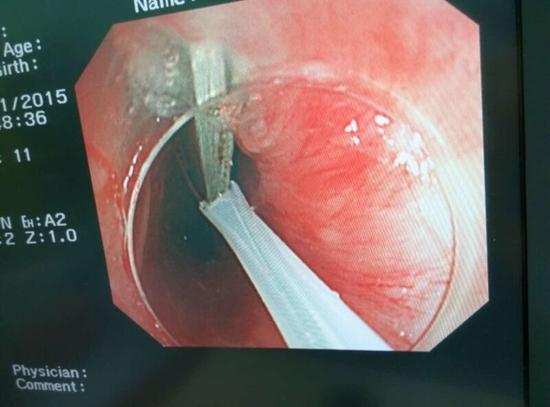

醫(yī)生從華先生胃里取出的鑷子和打火機(jī)

手術(shù)中,范醫(yī)生通過胃鏡準(zhǔn)確發(fā)現(xiàn)了胃里的鑷子。但讓他驚訝的是,在華先生胃底竟然還躺著三個(gè)被腐蝕了的打火機(jī),打火機(jī)的金屬部件都已經(jīng)不見了。

隨后,范醫(yī)生先用圈套器套取出了長(zhǎng)10厘米的鑷子,再一個(gè)一個(gè)地取出了打火機(jī)。整個(gè)取出過程小心謹(jǐn)慎而又一氣呵成,只用了不到10分鐘。